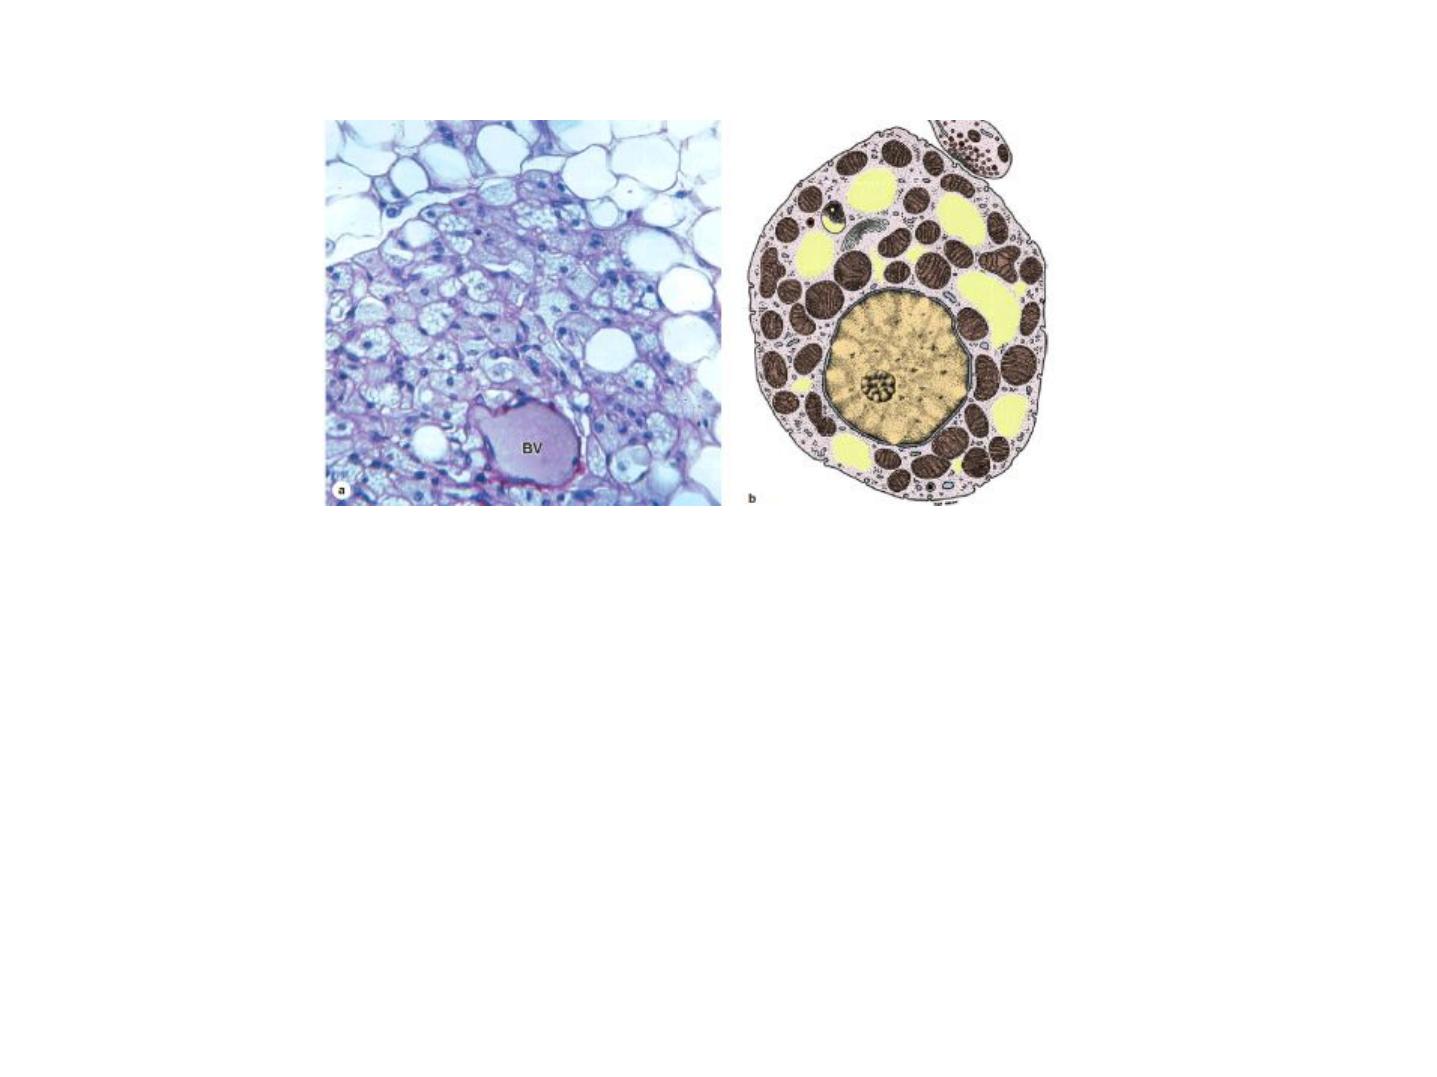

Figure 4: (a) Brown adipose tissue is shown here around a small blood vessel (BV)

and adjacent white adipose tissue at the top of the photo. Brown adipocytes are

slightly smaller and characteristically contain many small lipid droplets and central

spherical nuclei. If the lipid has been dissolved from the cells, as shown here, the

many mitochondria among the lipid spaces are reserved and can be easily

distinguished. X200. PT. (b) A diagram of a single multilocular adipocyte showing the

central nucleus, numerous small lipid droplets (yellow), and many mitochondria.